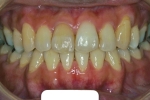

マルチブラケット終了時